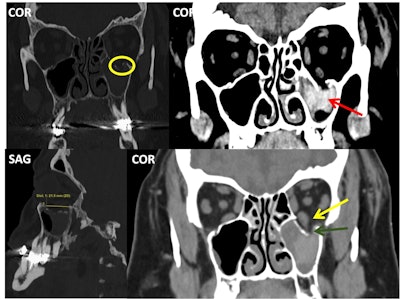

Pure and simple blow-out left orbital fracture; the orbital rim and internal orbital buttress remain unaltered. Over half of the orbital floor is involved (measurement in the lower left image), and the fracture line crosses the infraorbital canal (yellow circle). The left inferior rectus muscle (yellow arrow) looks asymmetrical when compared to the contralateral one and appears to be “tractioned” with accompanying intraorbital fibrofatty tissue into the left maxillary sinus (dark green arrow); the sinus also has hyperdense content compatible with a hematoma (red arrow).

The most common fractures are blow-out fractures involving the orbital floor or, less frequently, the medial wall. Acute inflammation and hemorrhage could either mask enophthalmos due to an orbital blow-out fracture or lead to an orbital compartment syndrome; both these conditions require surgical intervention, the authors noted.